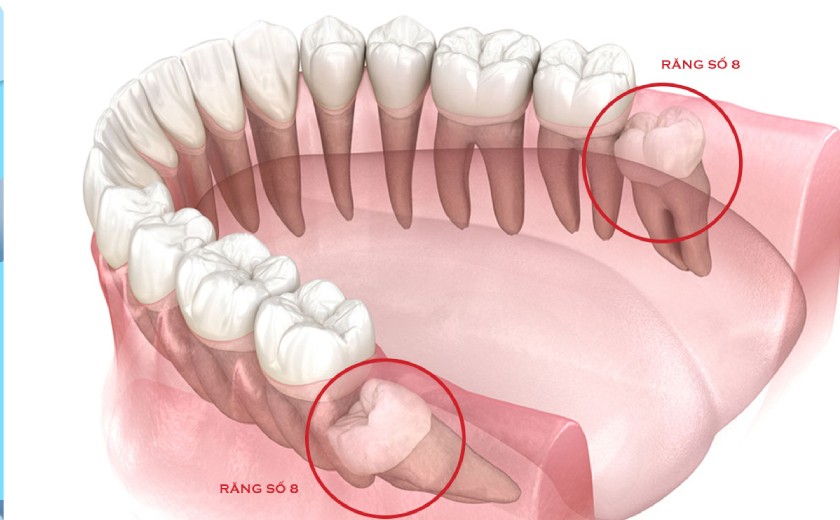

Răng khôn, hay còn gọi là răng số 8, là những chiếc răng mọc ở vị trí cuối cùng trên cung hàm. Thông thường, răng khôn xuất hiện khi chúng ta trong độ tuổi từ 17 - 25, khi xương hàm đã phát triển hoàn thiện. Một người có thể có từ 1 đến 4 răng khôn, thậm chí có những trường hợp không mọc răng khôn nào hoặc mọc thiếu.

Không giống như các răng khác, răng khôn thường mọc khi hàm đã không còn đủ chỗ, dẫn đến tình trạng mọc lệch, mọc ngầm hoặc mọc kẹt trong nướu. Điều này có thể gây đau nhức, viêm nhiễm hoặc ảnh hưởng đến răng bên cạnh.

Răng khôn, là những chiếc răng mọc ở vị trí cuối cùng trên cung hàm